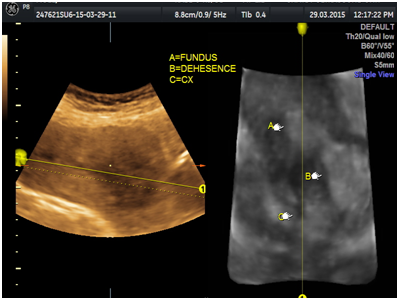

A 29-year-old multiparous woman at 11weeks’ gestation was referred to our hospital for termination of pregnancy due to suspected placenta accreta or cesarean scar ectopic by abnormal vasculature around lower uterine segment gestational sac on ultrasound. She had delivered 2male children by cesarean section. The patient underwent ultrasound due to complain of vaginal bleeding. It revealed lower uterine segment pregnancy with abnormal vasculature in the placenta bed suspicious of placenta accreta or cesarean scar ectopic pregnancy about 10weeks gestation (Figure 1). The decision was done to evacuate the pregnancy vaginally by surgical means. The patient underwent surgical evacuation under ultrasound guidance but severe vaginal bleeding occurred. The procedure was ended and uterovaginal packing was done for 24hrs. The patient was vitally stable. The procedure was performed transabdominal ultrasound examination after 24hrs that revealed bulky uterus with hematoma inside cavity and there was a defect (3cm×2.0cm) in the lower anterior uterine wall with no fluid collection in the abdomen (Figures 2-5). The patient was vitally stable with no vaginal bleeding. We removed the vaginal pack intraoperative under general anesthesia, prepared for laparotomy in case of severe bleeding. No bleeding occurred, the patient discharged after 1 week and follow-up after one month revealed normal uterus.

Figure 2 Transabdominal ultrasound revealing hematoma in the lower uterine segment after evacuation.

Figure 3Transabdominal ultrasound revealing defect in the lower anterior wall on 3D view.

Figure 4Uterine defect about 3cm.

Figure 5Hematoma intrauterine about 5cm.